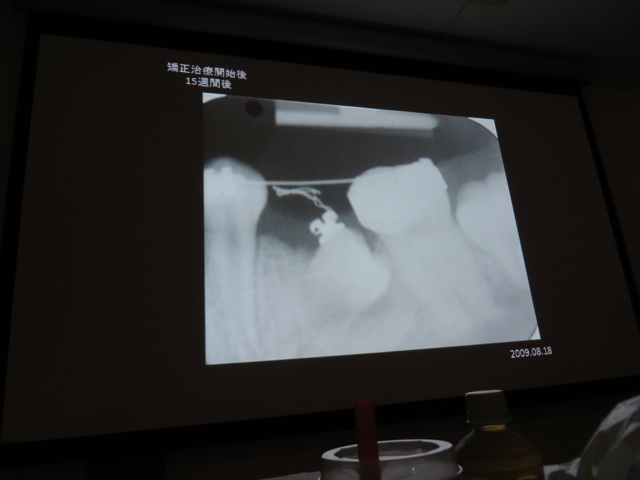

今回の矯正歯科研修会は様々なタイプの上顎前突症例に対するアプローチを学びました。

また乳歯列期からの経過観察と治療介入で正常咬合に導く咬合誘導の重要性についても学びました。